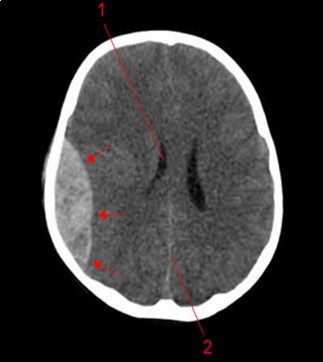

From the point of view of care, two (n=2) (10.52%) children received medical treatment compared to 17 (89.48%) children who received medical-surgical treatment. Neurosurgical treatment consisted of evacuation of the extra dural hematoma. This involved making a skin incision, trepanation (Figure 3 a), a preserved cranial bone flap, evacuation of the extra-dural haematoma (Figure 3 b), haemostasis either of the bone using bone wax or venous or arterial haemostasis by bipolar coagulation as appropriate, suspension of the dura mater (Figure 3 c), replacement of the bone flap (Figure 3 d) and finally suturing of the scalp in two planes. Figure 1, Figure 2, Figure 3.

Figure 1.Image of a brain CT scan without contrast, in a parenchymal window, axial view showing a right parietal extra dural hematoma associated with diffuse cerebral oedema, and subfalcorial brain schift